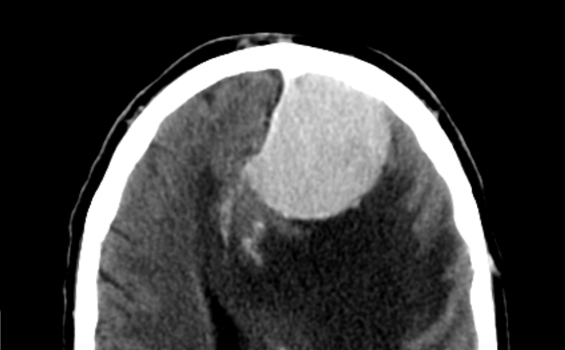

脑膜瘤3cm-4cm严重吗?脑膜瘤不开刀能活多久? 脑膜瘤(Meningiomas)是一种长在脑膜及脑膜间隙的的肿瘤,在颅内常见,80%以上脑膜瘤都是良性的肿瘤。典型的脑...

脑膜瘤严重吗?虽然其多呈良性,但如不加以治疗,脑膜瘤会给脑部施加压力,并导致并发症。良性脑膜瘤能活多久?这取决于患者的具体治疗情况...

脑膜瘤概况:脑膜瘤是中枢神经系统较常见的原发性肿瘤,约占中枢神经系统全部肿瘤的三分之一。脑膜瘤的发病率为7.44/100000,也就是说每十万人中有7个...

脑膜瘤是良性还是恶性?脑膜瘤是较常见的原发性中枢神经系统肿瘤,约占三分之一。脑膜瘤是一种起源于蛛网膜帽状细胞的中枢神经系统肿瘤。脑膜瘤约占...